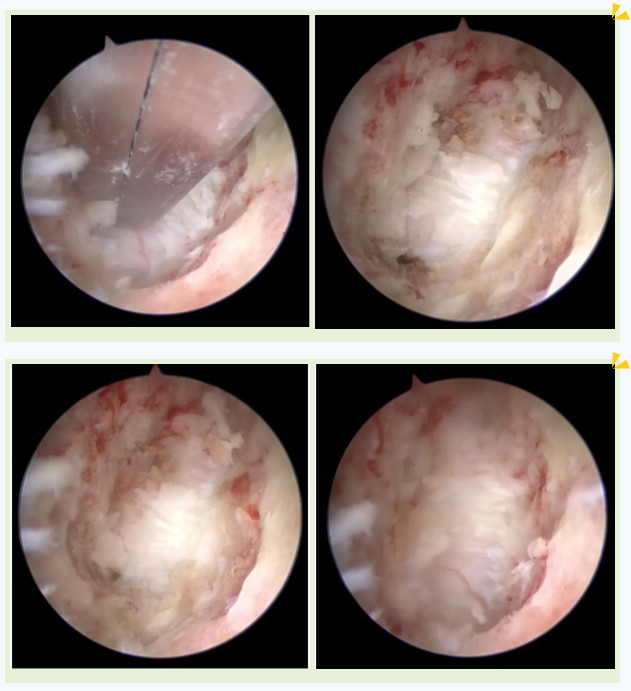

吳阿婆手術時的內(nèi)鏡下圖片

突破后縱韌帶后順利到達頸髓